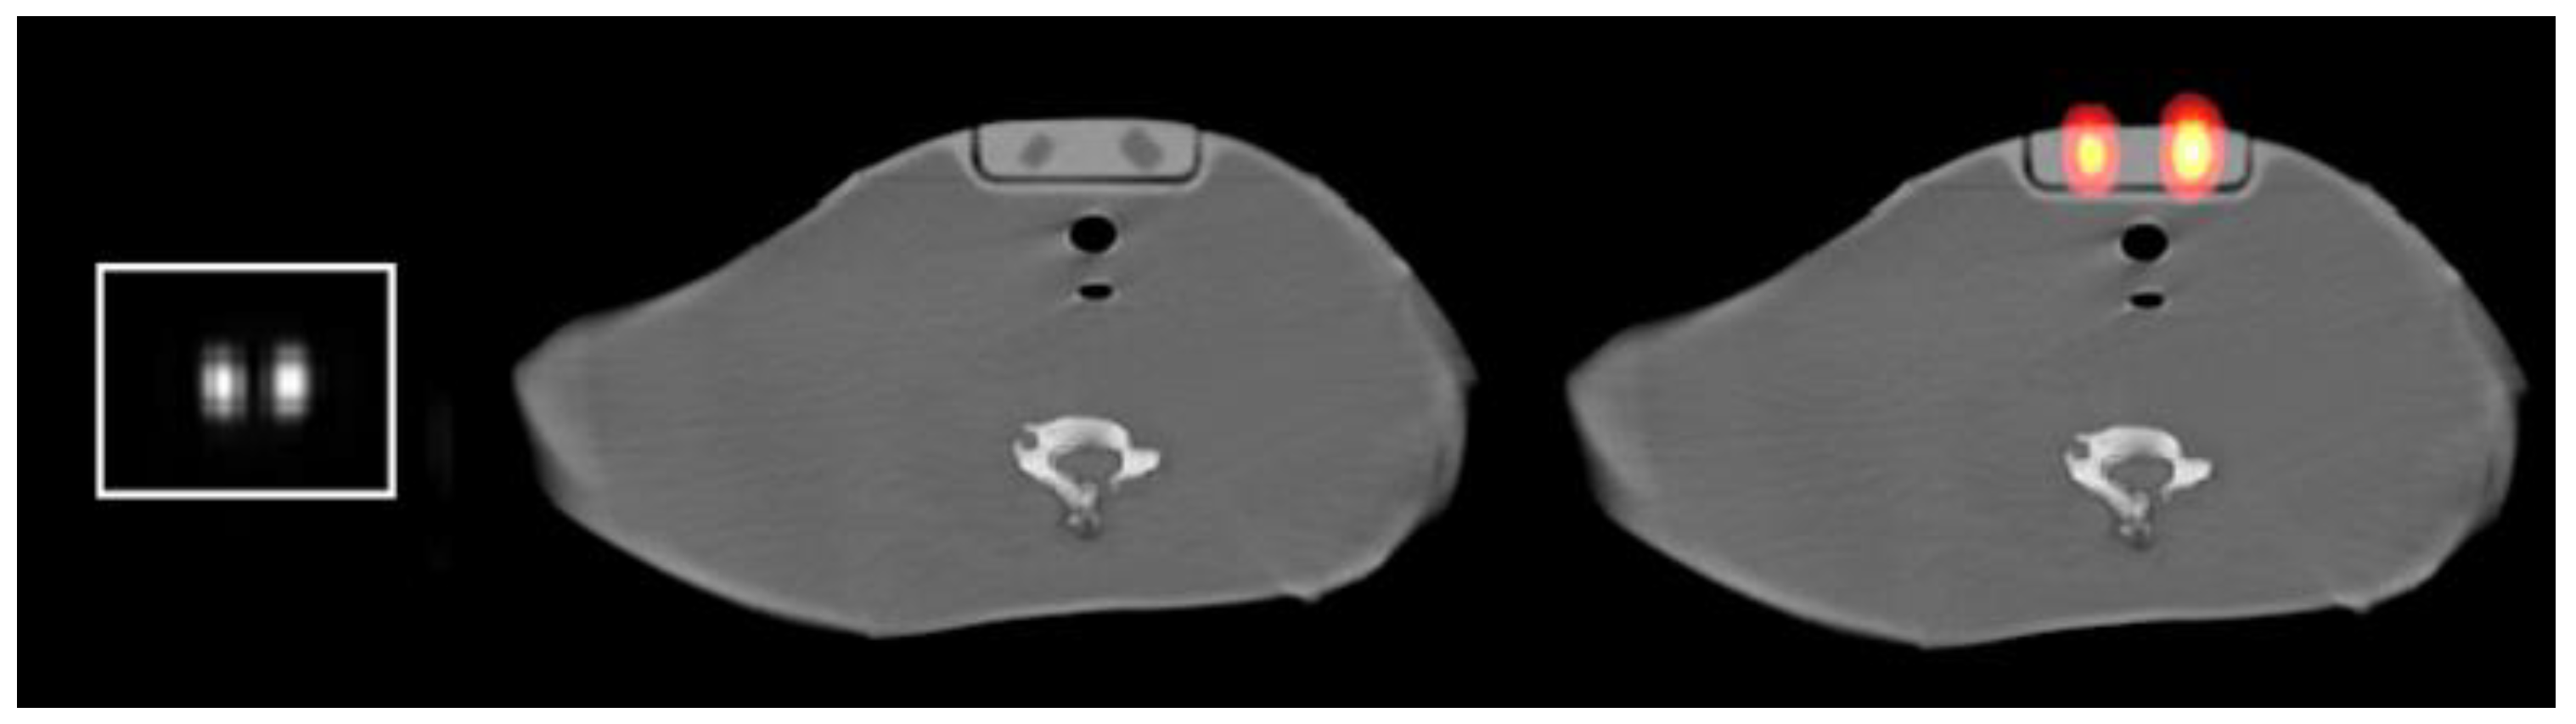

2.1. Method for Calculating Small Sizes of Volumes

2.1.1. Concept

2.1.2. MATLAB Calculations

2.1.3. Dependencies of the Gray-Level Histogram Technique